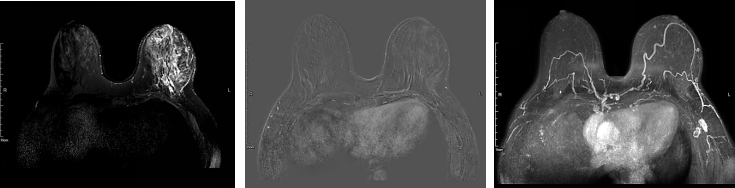

乳腺增强MRI提示左乳皮肤及乳晕增厚,乳头略凹陷,皮下腺体结构紊乱。左乳较右侧明显增大。左乳可见巨大肿块影,大小约12.3cm×6.7cm,T1WI呈等信号,T2WI呈稍高信号,局部DWI呈高信号,ADC减低,增强后明显不均匀强化,时间信号曲线呈平台型。左腋下可见多枚淋巴结影,最大者约2.1cm×1.4cm,BI-RADS 5(图4)。

图4.乳腺增强MRI

图7.新辅助治疗2周期后的乳腺增强MRI评估

图8.新辅助治疗6周期后的乳腺增强MRI评估